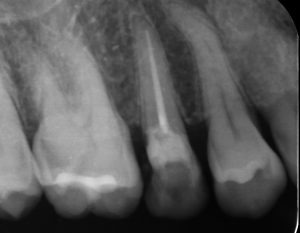

根管充填後

様々な器具や薬液を使用し、根管内を徹底的に洗浄します。この洗浄の工程が根管治療の成功に大きく影響します。洗浄後、根っこの中にお薬を詰めた後(根管充填)のレントゲンです。根っこの先までお薬が入っているのがわかります。当院では、根管充填材に体と相性が良く、殺菌効果の高いバイオセラミックを使用しています(保険診療では使用できません)。根管充填後、仮歯を入れて数ヶ月間経過観察をすします。レントゲンや患者さんの症状などから治癒が確認できてから最終的な被せ物を入れることで「被せ物を入れてから痛みが出た」という最悪の状態を防ぐことができます。